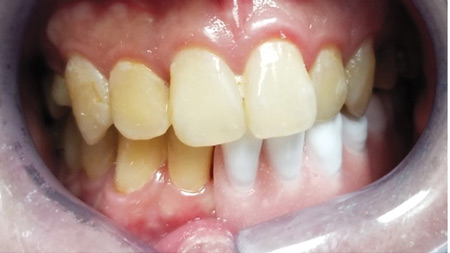

Silver diamine fluoride (SDF) has been used in caries prevention since the 1800s and has gained relevance in private practice since its FDA approval in the United States in 2015.1 While it is FDA approved for dentinal hypersensitivity, clinicians have been using SDF off-label for caries prevention and treatment, as it has been shown to stabilize … Read more

SDF in a restorative dental practice: A prosthodontist’s perspective